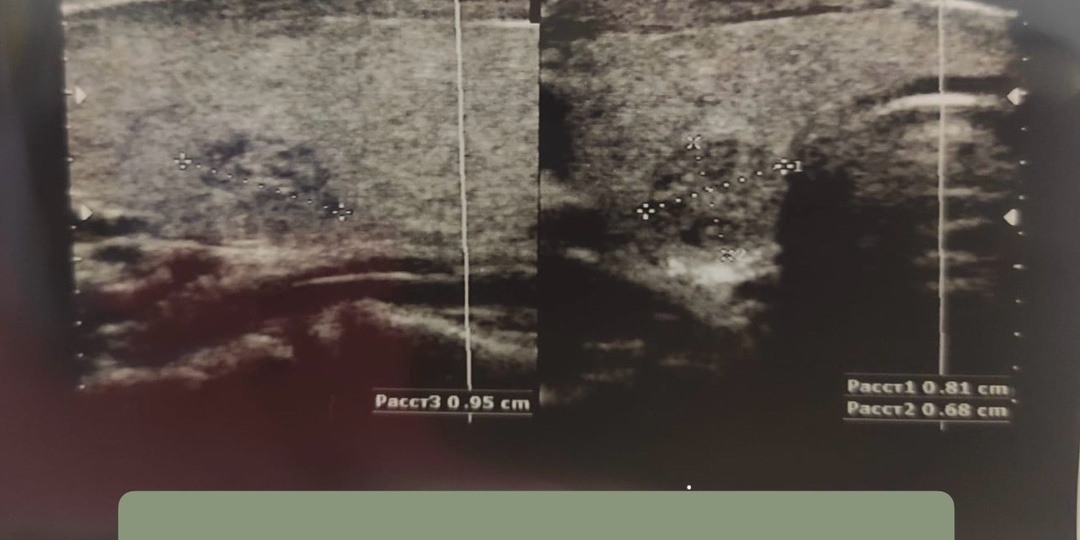

Что должно обязательно быть в описании УЗИ щитовидной железы

Часто мы с коллегами сталкиваемся с тем, что пациенты приходят с очень, мягко говоря, емким описанием исследования щитовидной железы. Самым странным заключением, с которым мы сталкивались, было просто «множественные образования щитовидной железы». Ни размеров, ни измерений, ни характеристик... В таком случае у врача один выход – отправить на повторное УЗИ щитовидной железы, даже к конкретным врачам – в ком мы уверены, что описание будет полным. Что делать, чтобы не попасть в ситуацию, где эндокринолог "развернет" с приема и отправит переделывать УЗИ? Коротко расскажу в этой статье. 1. Размеры щитовидной железы. Обычно это 3 измерения каждой доли + перешеек, иногда - с посчитанным общим объемом. 2. Структура ткани железы - однородная или нет. 3. При выявлении образований – их описание с обязательным указанием ряда параметров: - Локализации узла; в какой доле, в какой части доли, не выходит ли за пределы органа; - Размер узла: оптимально - в 3х проекциях, ну или хотя бы в 2х. Если отмеч